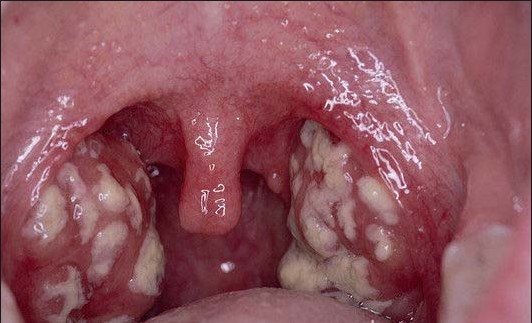

Возникает некротическая ангина (Симановского-Плаута-Венсана), которая сопровождается разрушением поверхностных тканей миндалин. На миндалинах появляется плотный белый налет. Очень важно вовремя распознать симптомы и начать соответствующее лечение, так как данное заболевание является заразным.

- Обнаружение белого оттенка налета на миндалине. Его можно заметить при хорошем освещении, имея под рукой зеркало и ложку.

- Увеличение толщины налета. Происходит это за счет быстрого накопления и отсутствия эффективного лечения. В таком случае на миндалине может образоваться пленка.

Для постановки дифференциального диагноза большое значение имеет клиническая картина с характерными признаками ангины Венсана, включающими в себя:

- поражение лишь одной миндалины, с заметной эрозией ее поверхности;

- под налетом на гланде находится кровоточащая поверхность;

- хотя миндалины выглядят ужасно, но острые болевые ощущения при глотании отсутствуют, и лихорадки либо не наблюдается вовсе, либо она незначительна.